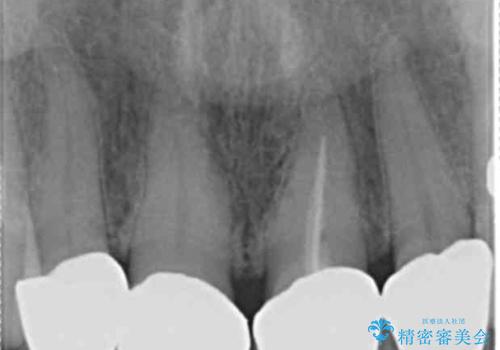

- 前歯のセラミック治療から5年経過した患者様です。

数年ぶりにメンテナンスに来て下さいました。

治療した上の前歯4本は全く問題がないそうで、「どうしてこんなに長持ちするんですか?」と聞かれた程です。

5年前のクラウン装着時と比較したところ、歯肉が成熟し歯間乳頭ができており、より天然歯のように自然に見えました。

患者様の良好なセルフケアと精密な適合の良いクラウンにより、歯肉の腫脹や退縮も認められませんでした。